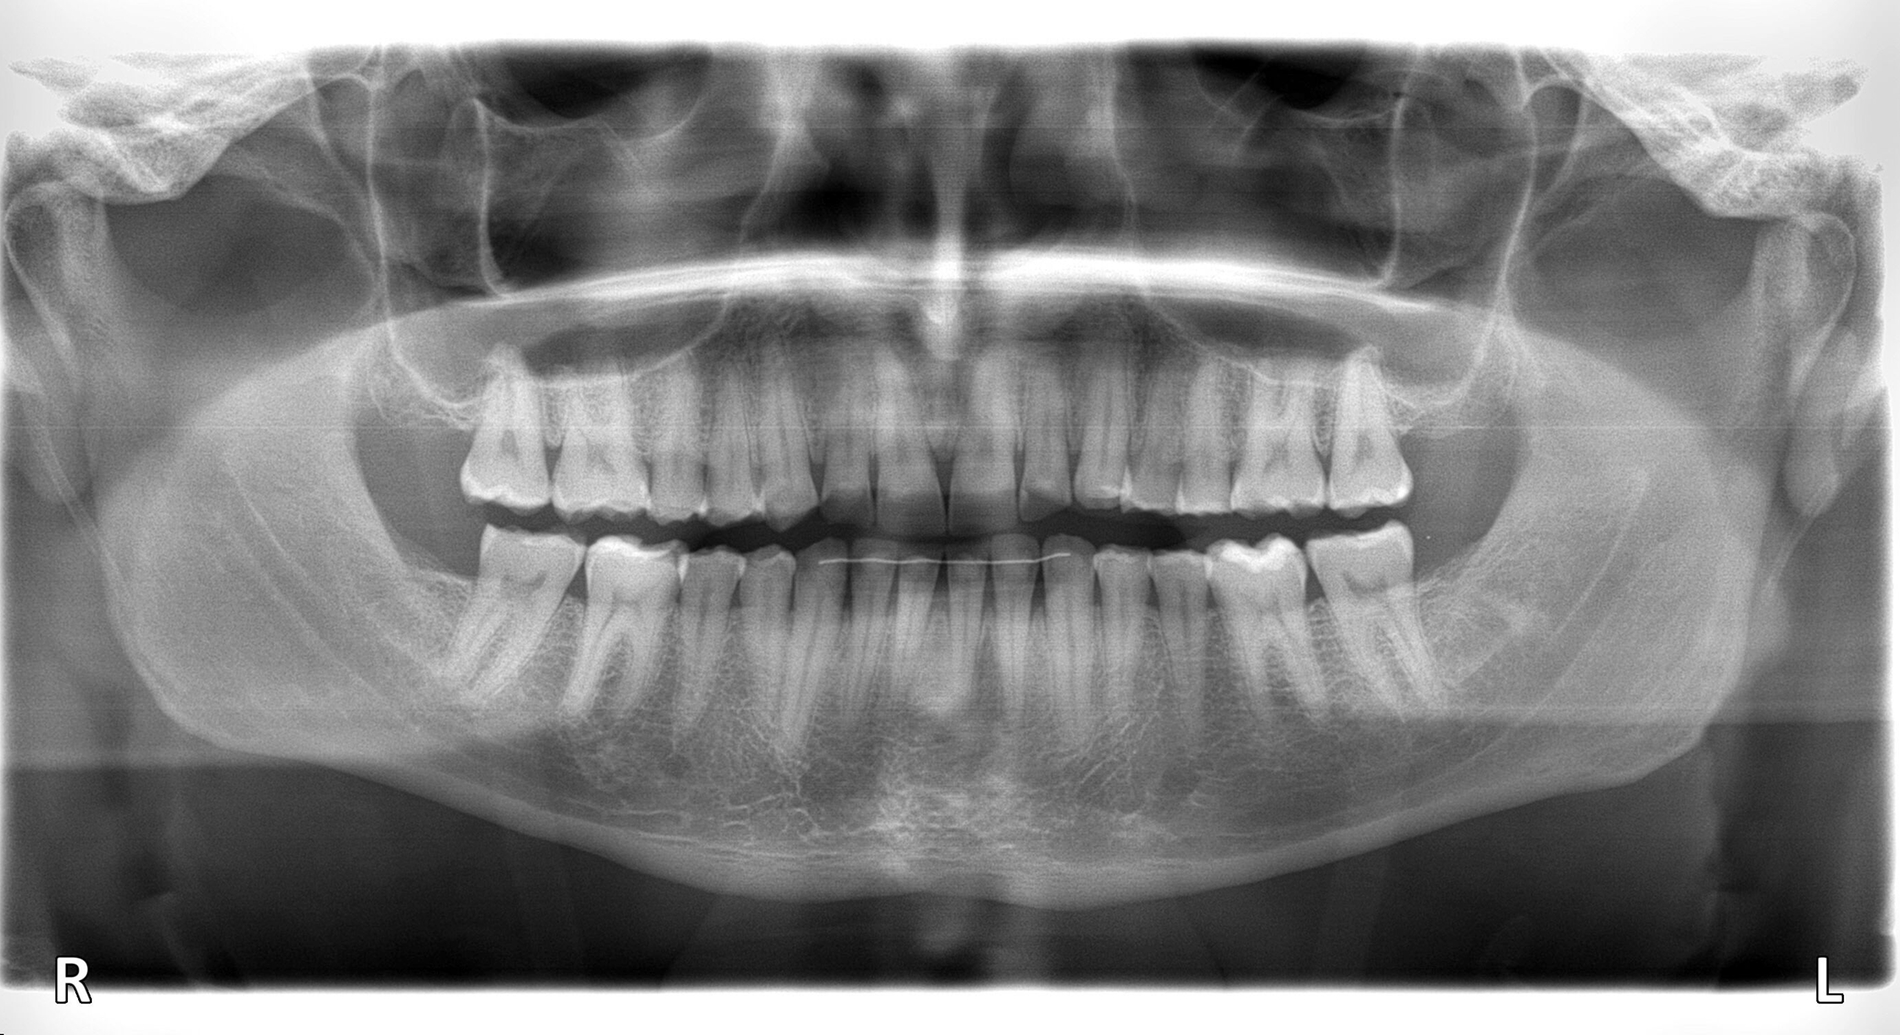

Diagnostik

Klinisch präsentierte sich ein vollbezahntes Gebiss ohne Weisheitszähne mit Defekten an der Zahnstruktur teilweise bis ins Dentin. Es waren deutliche Erosionsspuren zu erkennen, die auf die säurehaltige Ernährung im Kurzzeitintervall zurückgeführt wurden. Der BEWE-Index war mit dem Wert 13 auffällig und kategorisierte den Schaden als ausgeprägte Erosionen. Die Zähne 14, 13 und 24 wiesen nicht-kariöse zervikale Defekte auf, diese treten häufig im Zusammenhang mit Bruxismus auf [Pecie et al., 2011]. Das CMD-Screening der Deutschen Gesellschaft für Funktionsdiagnostik und -therapie (DGFDT) [DGFDT, 2024] war unauffällig, da der Patient über keinerlei Schmerzen oder Beschwerden bei Kieferbewegungen klagte. Die manuelle Strukturanalyse (MSA) nach Bumann [Fasold und Kordaß, 2012] ergab bei diesem Patienten ein myofaziales Schmerzsyndrom. Im Prämolarenbereich imponierten Zahnhartsubstanzdefekte, die Hinweise auf starkes und häufiges Zähnepressen geben. Den Patienten selbst störten seine kälteempfindlichen Zähne sowie die Gesamtästhetik aufgrund des massiven Substanzverlustes.